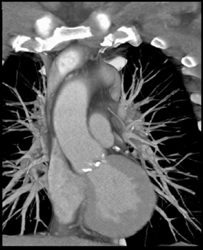

Thyroid Cancer Invades the Right Subclavian and Carotid Aa